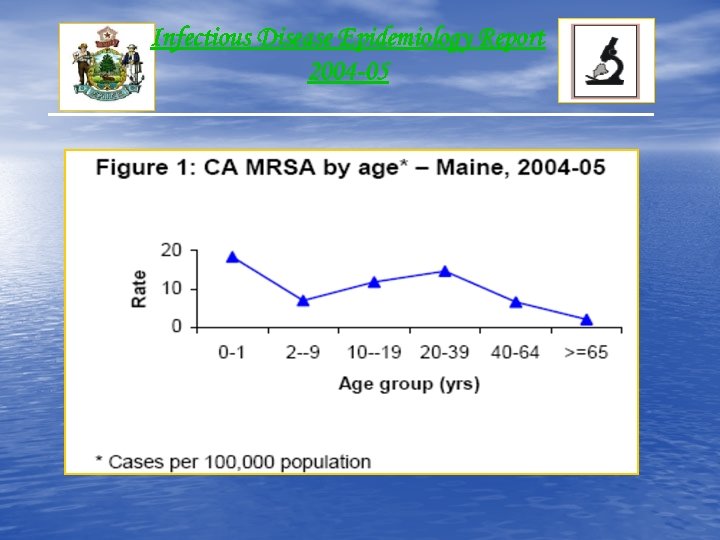

Infectious Disease Epidemiology Report 2004 -05 • Annual Average: 111 Cases • Incidence Rate: 8. 6 cases/100, 000 Population • Gender: Male (57 %) • Race: 94% White “Information available for 68 cases”

Infectious Disease Epidemiology Report 2004 -05 • Annual Average: 111 Cases • Incidence Rate: 8. 6 cases/100, 000 Population • Gender: Male (57 %) • Race: 94% White “Information available for 68 cases”

Infectious Disease Epidemiology Report 2004 -05

Infectious Disease Epidemiology Report 2004 -05